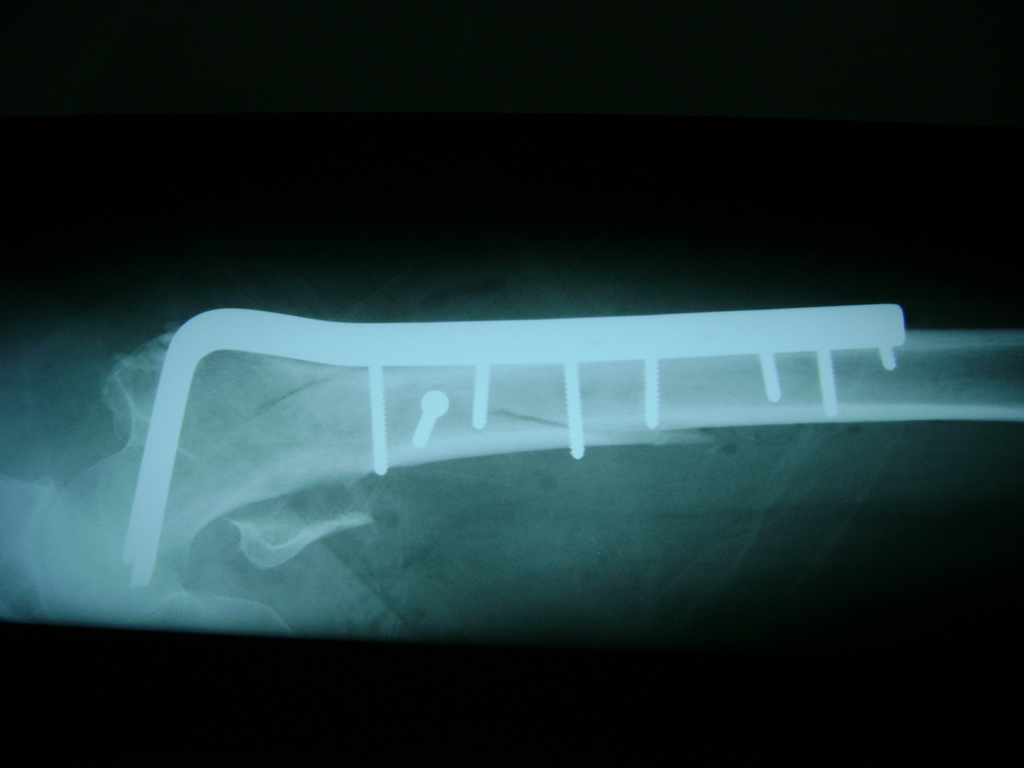

A menudo se recomienda la cirugía para reparar la fractura debido a dichos riesgos.